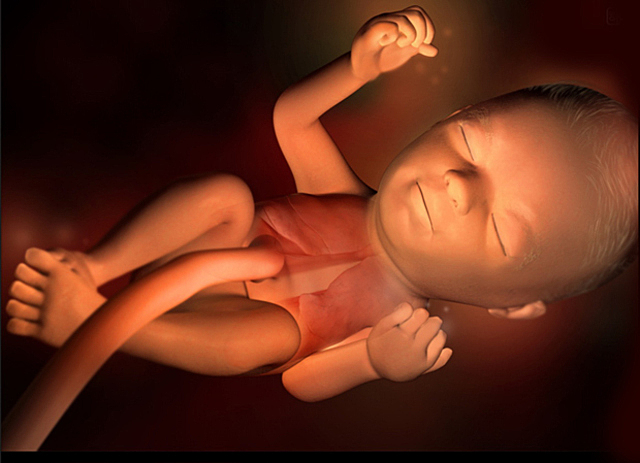

Ahora ya se han formado todos sus órganos y están funcionando corazón, cerebro, hígado, riñones e intestinos. Irán creciendo y desarrollándose continuamente hasta el nacimiento pero ya es posible reconocerlos perfectamente definidos.

Mide entre 28 y 29 mm y pesa casi 5 gramos, comienza la formación de codos y rodillas. Esta semana es la última que se le llamará embrión, después pasará a ser feto. Ya se encuentra totalmente formado, ahora solo falta la maduración.

• Onceava semana

Onceava semana

A las 11 semanas de embarazo el bebé pesa aproximadamente 8 gramos y pesará entre 4 y 6 centímetros.

Sus dedos están ya separados, las membranas que los unían han desaparecido. Aunque su cabeza sigue siendo la mitad de su cuerpo es completamente normal en este momento. Las orejas van migrando a su posición definitiva y el pequeño ya puede abrir y cerrar sus manos.